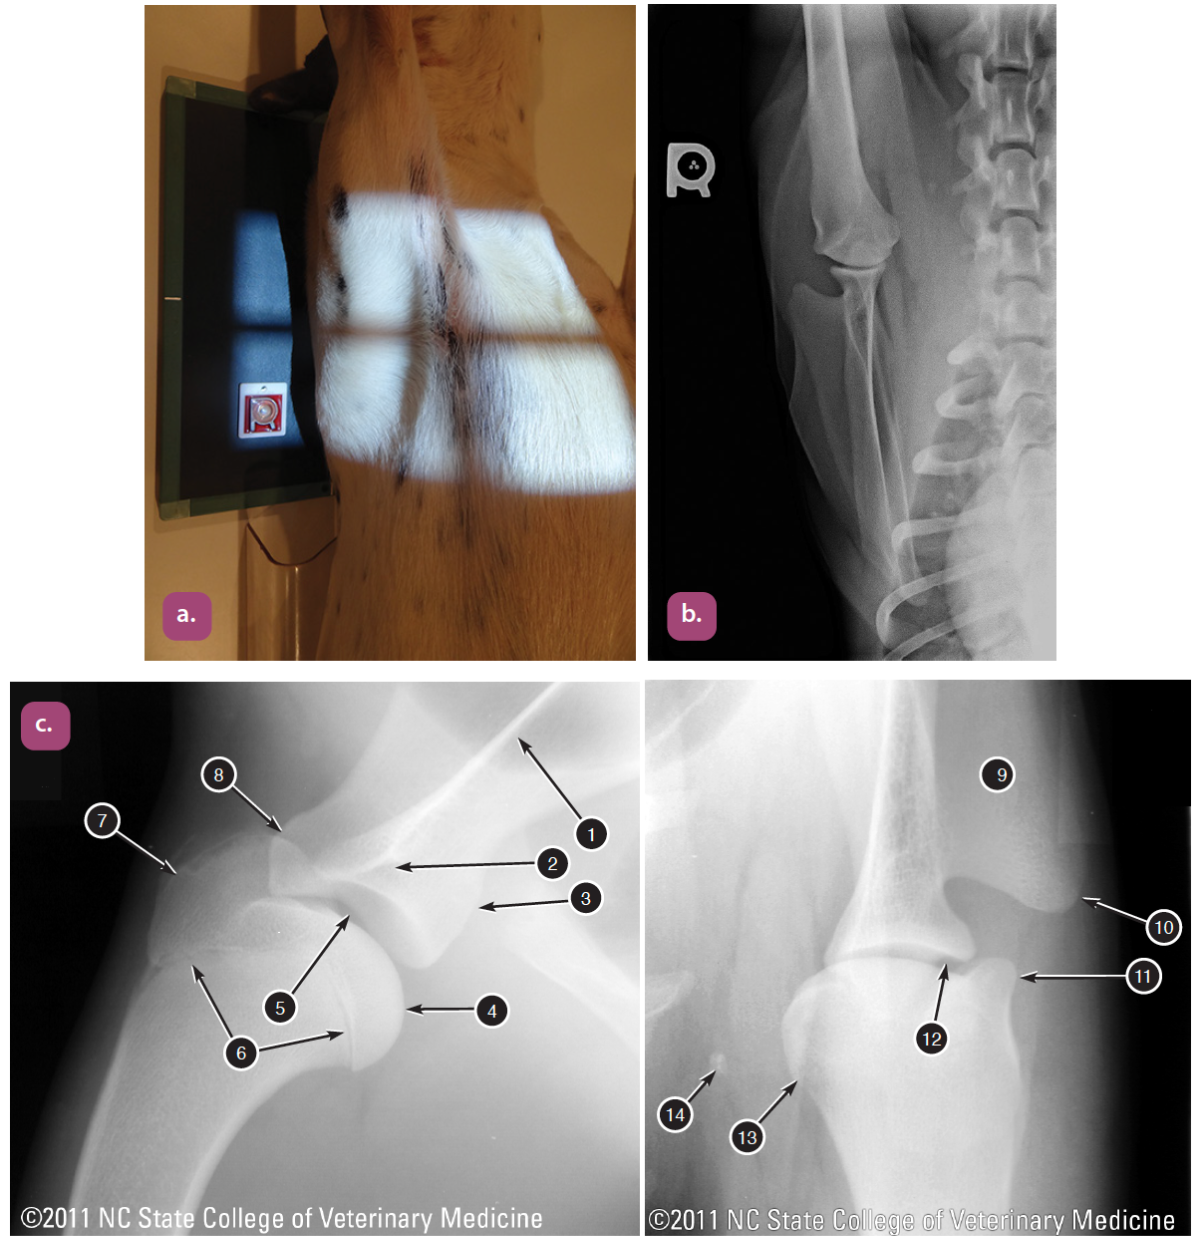

lateral projection of the pelvis

ventrodorsal extended hip projection

ventrodorsal frog leg projection